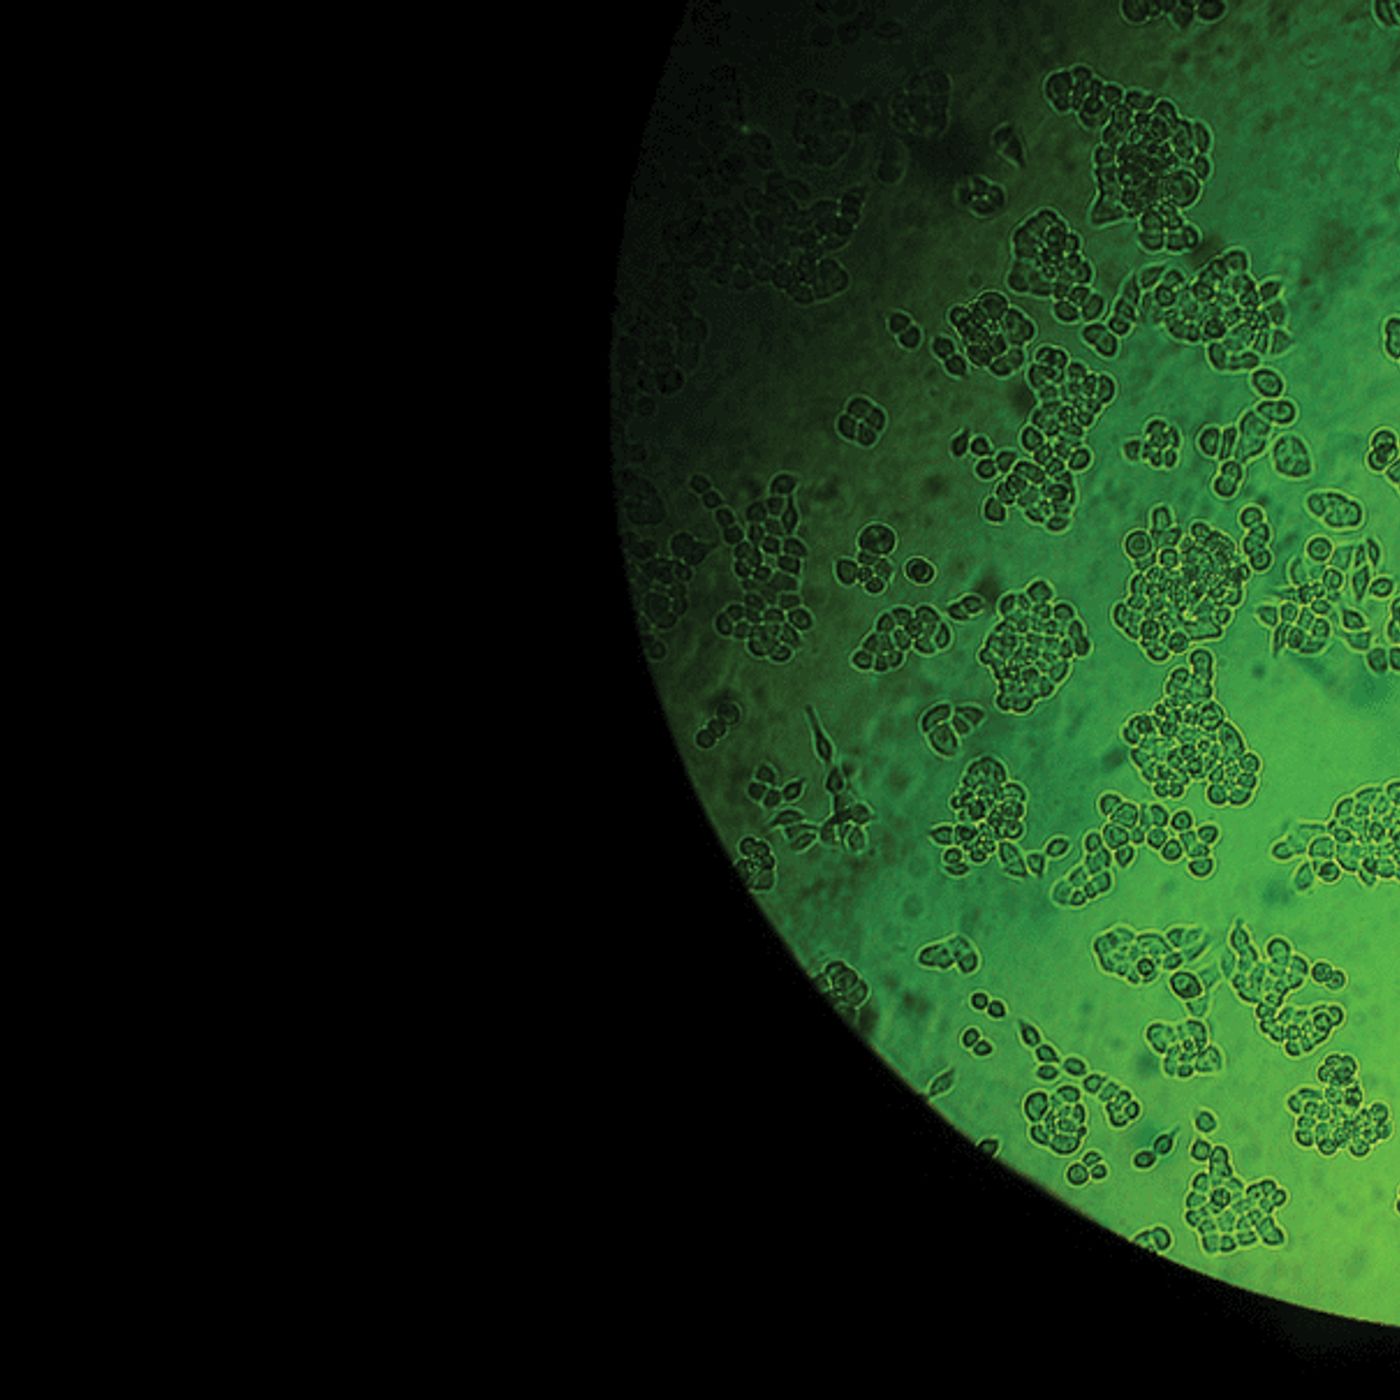

When we first released Famous Tumors, Rebecca Skloot's book about the life and legacy of Henrietta Lacks (and her famous cells) had just hit the shelves. Since then, some interesting things have happened to both Henrietta's cells and her family. So, 4 years later, we have a newly updated show!